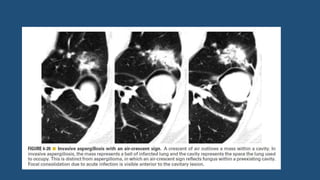

Air crescent sign and mycetoma

• Presence of a lung mass capped by a crescent of air.

• Usually indicates the presence of a mass within a cavity.

• Most typical of mycetoma.

• On CT, a round or oval mass (the fungus ball) can be seen in a

dependent location within the cavity and is typically mobile. The mass

is capped by a crescent of air.